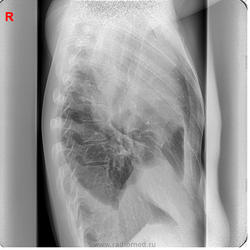

Мужчина 28 лет. Болен около месяца. В первую неделю заболевания была лихорадка. Практически не лечился. Всё время работал.

Беспокоит сильный кашель, 2 недели назад с гнойно-кровянистой мокротой, последние дни кашель до рвоты, из-за которого почти не ест и может спать только на правом боку, мокрота скудная, светлая. Похудел, слабость, одышка при небольшой нагрузке.

Сегодня решил проверить своё здоровье на флюорографии. Предыдущая флюорография 6 лет назад.

центральный рак, ателектаз верх. доли

На мой взгляд, центральный рак + параканкрозная пневмония + базальный параканкрозный плеврит.

"может спать только на правом боку"-патогномоничный признак полости(-ей). предположу: была пневмония (лихорадка),к-ая абсцедировалась (не лечился).абсцесс прорвался (мокрота,кашель до рвоты), содержимым обтурировался в\д бронх,вследствие чего возникла гиповентиляция верхней доли. Ну и экссудативный плеврит в довесок

Я рассуждал почти также. Только настоящего ателектаза, пожалуй, нет. Написал: "Абсцедирующая пневмония без дренирования абсцесса в настоящее время, с ателектатическим компонентом. Экссудативный плеврит есть и свободный и осумкованный. Линейку сделать можно, но надо сперва пролечить, получить динамику. Для начала в прорыв брошена кавалерия…, ну терапевты, значит.

Поддержу недренированный абсцесс/абсцедирующую пневмонию. Ну, и гидроторакс, конечно.

Интересное наблюдение. Поддерживаю 3 последних поста. ИМХО:скиологически, корректно  вести речь, о выраженном выпоте в плевральной полости с осумкованием, частичном  компрессионном ателектазе верхней доли.Субстратом пневмонии, по видимому является округлый инфильтрат в прикорневом отделе ( абсцесс который конечно, недренировался, т.к. в случае дренирования был бы виден уровень жидкости) и  перибронхиальная инфильтрация в нижнем поле.

При недренированном абсцессе такого размера у молодого человека была бы лихорадка под 40 и не только в первую неделю заболевания. Как вариант предлагаю рассмотреть саркому правого лёгкого.

доб.сн.: на прямом и на боковом - симптом ампутации в\долевого бронха= явление ателектаза в\доли, в которой начался распад (участок просветления на прямом). Центральный...как-то сомнительно, лимфосаркома...и всего 28

Со схемой в передней проекции могу согласиться, но не в боковой. Не должен так располагаться верхнедолевой бронх, тем более если ампутирован. А может быть, его и нет? Мне тут трахеальный бронх почудился…. Как Вам такая схема?